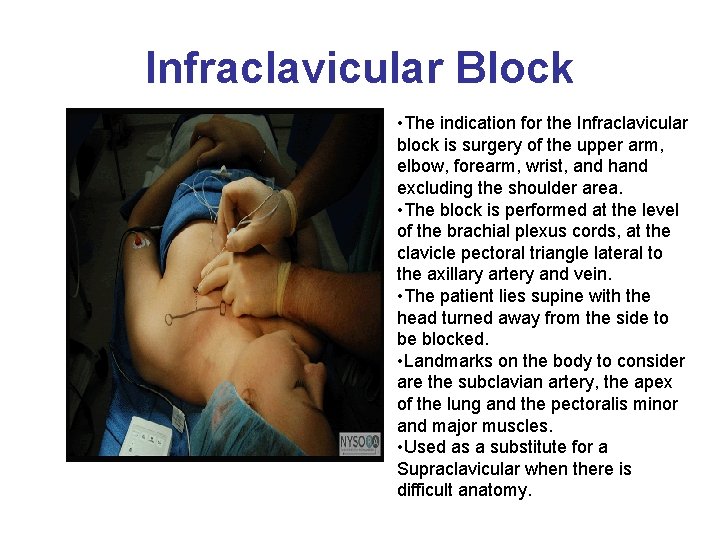

Infraclavicular Block • The indication for the Infraclavicular block is surgery of the upper arm, elbow, forearm, wrist, and hand excluding the shoulder area. • The block is performed at the level of the brachial plexus cords, at the clavicle pectoral triangle lateral to the axillary artery and vein. • The patient lies supine with the head turned away from the side to be blocked. • Landmarks on the body to consider are the subclavian artery, the apex of the lung and the pectoralis minor and major muscles. • Used as a substitute for a Supraclavicular when there is difficult anatomy.